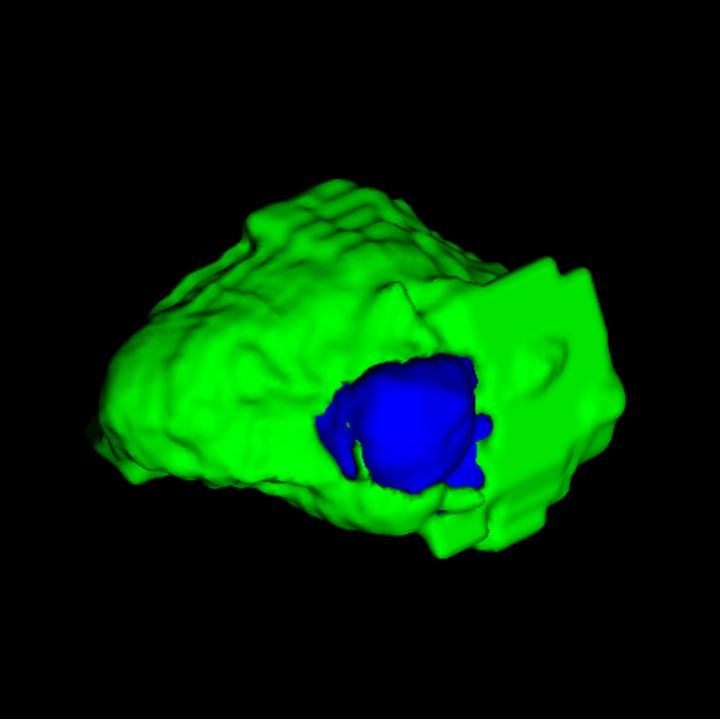

Tumour Information Preservation. For the brain tumor segmentation, we use a Swin UNETR model[27, 70], trained with random rotation, and intensity as data augmentation. In Figure 5, we highlight the tumor profiles of the generated MRIs compared to the ground truth tumour profile. In the test set with human ground-truth annotations (), the real MRI Dice score is 85.15 while the generated MRIs from a single slice have a dice score of 83.09. This shows how the generated MRIs indeed preserve the tumor information and can act as an affordable and informative pseudo-MRI, before conducting an actual costly MRI examination in hospitals.

B.4 Tumour Information Preservation

On the test set with human ground-truth annotations (), the brain volumes generated from single slice input preserve the volume of the different tumour components (paired t-test, for all 3 classes) (see Table 3). The real MRI Dice scores are put for reference to our generated MRIs. X-Diffusion outperforms baselines TPDM [36] and ScoreMRI [18] in tumour preservation (see Table 3 and Figure 12). We ran experiments comparing the tumour segmentation Dice Score varying X-Diffusion configurations. The multi-slice input X-Diffusion achieves a marginally better Dice Score than the single-slice input model (83.47 83.09). We also ran experiments with slice input used for volume reconstruction intersecting or not with tumour. We observe on average a drop of 6% Dice Score (see Table 3). Further away from the tumour the input slice for volume reconstruction is selected, and we observe a linear decrease in tumour segmentation Dice Score with the lowest value of 77.21 Dice Score (see Figure 15).

This shows how the generated MRIs indeed preserve the tumour information and can act as an affordable and informative pseudo-MRI, before conducting an actual costly MRI examination in hospitals. Given that our model has been trained on brain scans all with tumours, we expect to see hallucinations of tumours in healthy scans. We report two cases of failure of our model in Figure 16. Hallucinations of tumours on healthy samples represent 2% of the test set.